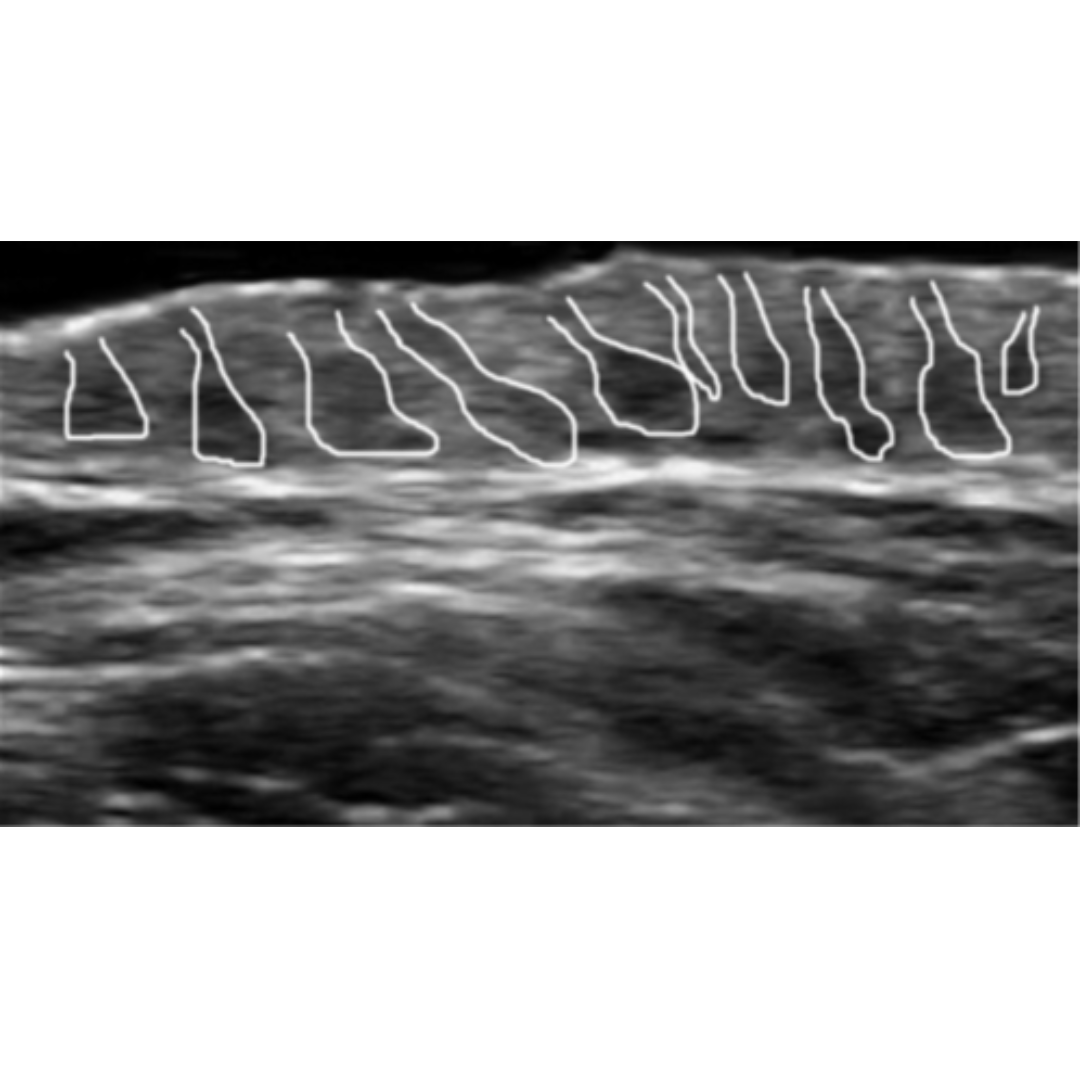

Figura 1: Imagen de ecografía de la región axilar que muestra el ensanchamiento de la parte superior de los folículos pilosos. (Signo de botella de Champagne)

Visualización de tractos pilosos

Los tractos pilosos se observan como imágenes lineales hiperecogénicas dentro de la colección liquida.